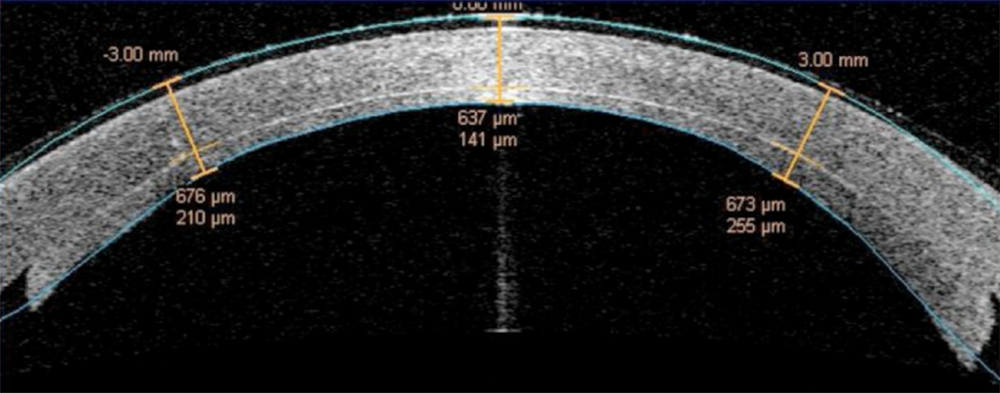

The next images show DSAEK and DMEK transplants. Notice how easy it is to see the DSAEK transplant in the eye, because it has a layer of stroma with it.  DMEK is almost impossible to see unless it is not fully attached yet.  This image of a partially separated DMEK is shown here just so that you can appreciate how thin the graft is when no stroma is transplanted.  You can see how important these grafts are to the cornea, because any area that doesn’t have the graft attached will swell thicker than other areas of the cornea.